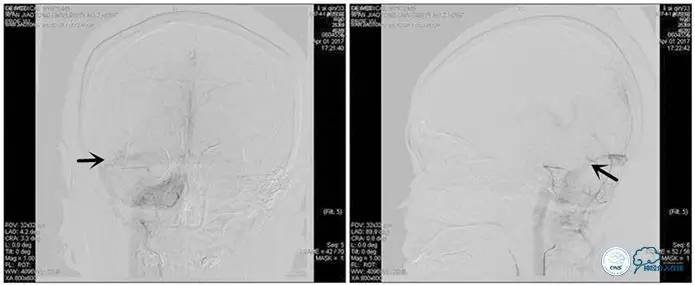

诊疗方案:为挽救视力,确定支架成形术效果,急诊行右侧横窦乙状窦狭窄球囊扩张术(6mm×20mm,Ever Cross )。

术中测压

远端压力:530mmH2O

近端压力:120mmH2O

术中造影

术后造影

狭窄较前有改善